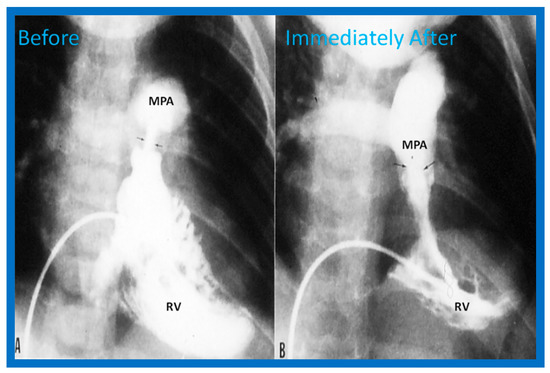

3.1. Pulmonary Stenosis

4.1. Pulmonary Stenosis

Pulmonary Stenosis in the Fetus